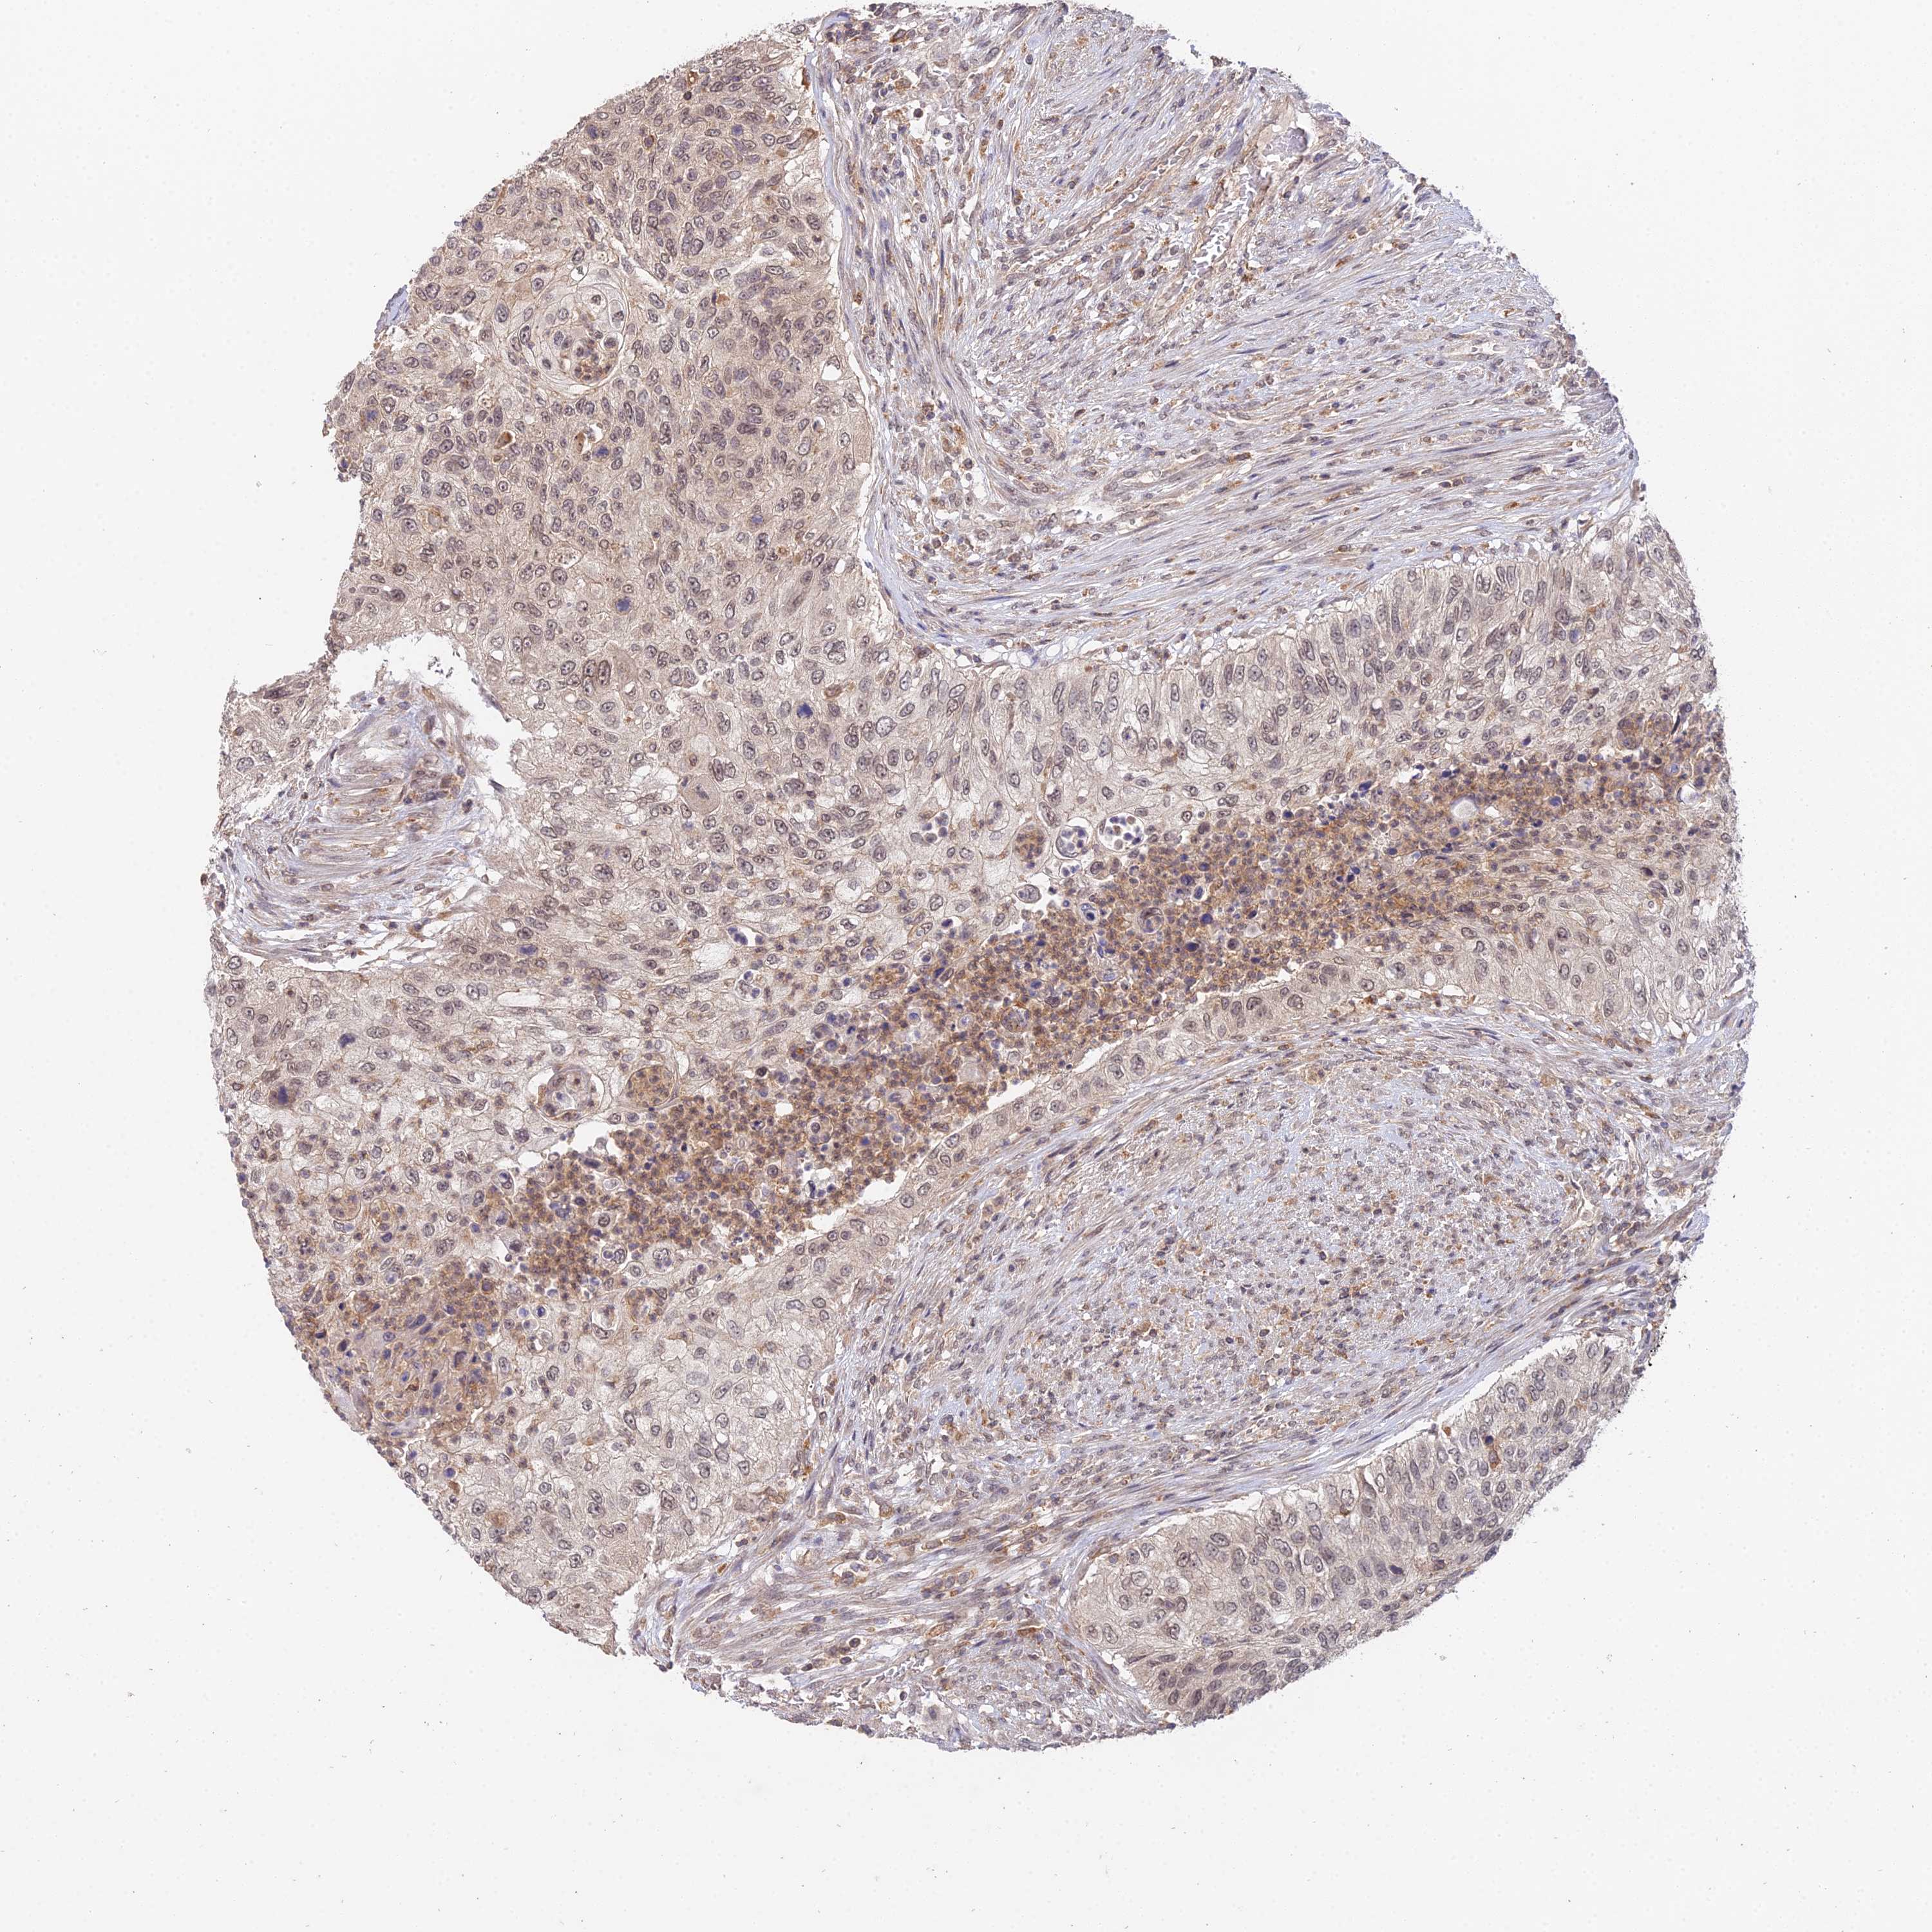

UROTHELIAL CANCER - Protein expressioni

A mouse-over function shows sample information and annotation data. Click on an image to view it in a full screen mode. Samples can be filtered based on level of antibody staining by selecting one or several of the following categories: high, medium, low and not detected. The assay and annotation is described here.

Note that samples used for immunohistochemistry by the Human Protein Atlas do not correspond to samples in the TCGA dataset.

Antibody stainingi

Antibody staining in the annotated cell types in the current human tissue is reported as not detected, low, medium, or high, based on conventional immunohistochemistry profiling in selected tissues. This score is based on the combination of the staining intensity and fraction of stained cells.

Each image is clickable and will lead to virtual microscopy that enables deeper exploration of all samples and also displays staining intensity scores, fraction scores and subcellular localization as well as patient and tissue information for each sample.

Antibody HPA044922

Staining

High

Medium

Low

Not detected

Intensity

Strong

Moderate

Weak

Negative

Quantity

>75%

75%-25%

<25%

None

Location

Nuclear

Cytoplasmic/membranous

Cytoplasmic/membranous,nuclear

Urothelial carcinoma, High grade

Urothelial carcinoma, Low grade